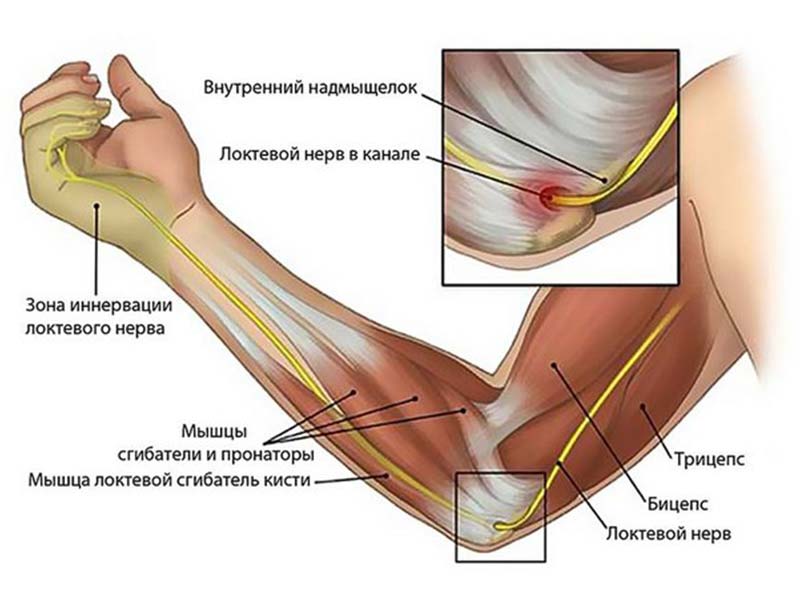

Нервные волокна

Нервные волокна локтя в ответе за чувствительность и движение пальцев. Три нервных отростка обеспечивают питание мышцам, которые совершают движения в соединениях локтя:

- лучевой нерв и срединный — проходят по передней стороне локтя;

- локтевой — длинный нерв плечевого сплетения. Волокна 7 и 8 позвонков шейного отдела отходят из плечевого сплетения, проходят внутри задней стороны руки до пальцев кисти.

В локте и канале Гийона лучезапястного сустава защемляются нервные волокна. Нервный ствол идет по сухожильно-костным каналам. Воспаления и травмы приводят к защемлению. Чувствительные и двигательные волокна вызывают онемение, боли и ограничения движений при поражении нерва. Туннельный синдром развивается при деформации костей, хрящей или сухожилий.

Воспаленная мышца, связка или новообразование мягких тканей зажимают нервные волокна, так как лежат поверхностно и доступны внешнему воздействию. Прострелы, боль и онемение достигают пальцев при ударе локтя. Нарушение двигательной функции и питания приводят к атрофии мышц и постепенному изменению кисти.

Атрофия и утрата движений мышцами области предплечья и кисти — следствие поражения нерва выше средней трети предплечья. Травма канала Гийона приводит к слабости в области пальцев кисти. Обращение к врачу и начало лечения помогут избежать осложнений.

Последствия защемления нерва приводят к утрате трудоспособности, боли и в конечном итоге к оперативному вмешательству.